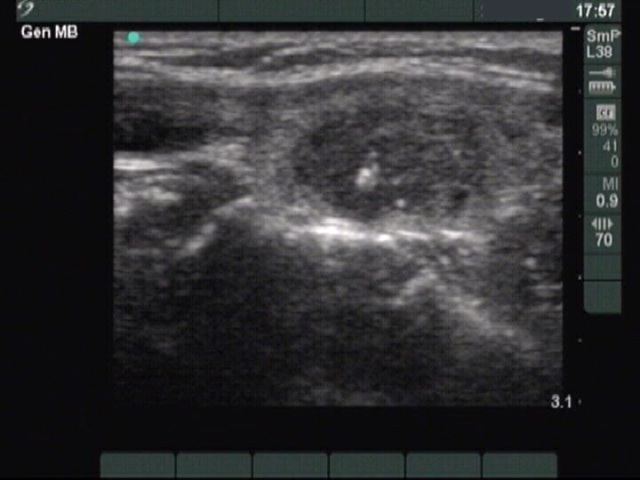

Medullary carcinoma (histological diagnosis) - case 1774

This tumor contains numerous amyloid deposits. The images were gained with an older equipment, therefore the bright granules within the echonormal background of the patches are larger because of the low quality resolution.